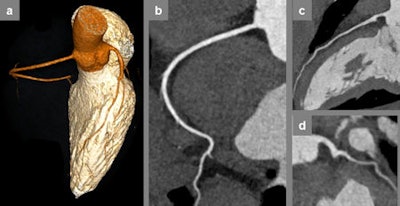

performed during free breathing with a tube voltage of 80 kVp at a mean heart rate of 51 bpm, resulting in a dose length product of only 24 mGycm. All images courtesy of Dr. Bernhard Bischoff.

The Munich team evaluated the potential of high-pitch CCTA in free-breathing patients when compared with breath-holding patients in 40 patients (20 breath-holding and 20 free-breathing patients) with a heart rate of 60 bpm or below. Mean heart rate during image acquisition was 52 ±5 bpm in both groups. The mean age of the breath-holding group was 57 ± 18, and 13 (65%) were men, while the mean age of the free breath patients was 55 ± 18, and 11 (55%) were men.

There was no significant difference in mean image quality, slightly favoring image acquisition during breath-holding. The mean image quality score 3.76 ± 0.32 in breath-holding patients compared with 3.61 ± 0.45 in free-breathing patients (p = 0.411). Due to a smaller amount of injected contrast medium, there was a trend for signal intensity to be slightly lower in free-breathing patients, but this was not statistically significant (435 ± 123 HU vs. 473 ± 117 HU; p = 0.648), the authors explained.